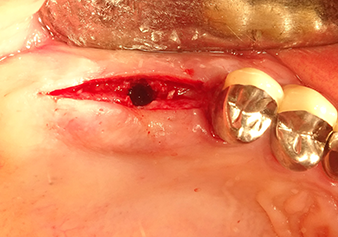

The I2A instrument (diameter 2.0 mm) was then used to perforate the sinus floor intermittently and on the smallest scale possible. This special piezosurgical method ensures that the Schneiderian membrane is not damaged. When the Z25P was used, the membrane was already lifted slightly by the coolant supplied via the instrument tip (Fig. 3). The coolant quantity was just 50% in order to avoid high pressure in the implant bed.

Implant bed preparation and augmentation

Following an intermediate check (Fig. 4) a further preparation step was performed (Fig. 5). Afterwards, the hydraulic Z35P instrument was used to lift the membrane to the desired position (Fig. 6 and 7). This was followed by further piezosurgical preparation of the implant bed, concluded with a rotary bur and shoulder milling cutter up to the implant diameter of 4.8 mm. Before the implant was inserted, the augmentation material (particle size approx. 0.8-1.6 mm) was introduced underneath the Schneiderian membrane (Fig. 8).